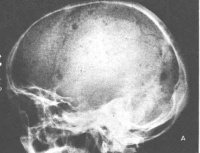

x线骨骼检查:受累骨骼示圆形穿凿样缺损,以颅骨为典型。也可见弥漫性骨质疏松及脱钙。

骨髓瘤患者骨骼溶骨现象

X线主要表现为多个溶骨性破坏和广泛的骨质疏松

x线检查时,在被累的骨质中,可以发现多数溶骨性穿凿形缺损,周围无反应性新骨增生,此为骨髓瘤的特点。所以病理性骨折较多。椎体发病时,则产生压缩骨折。四肢发生病理性骨折时,可以引起小量骨膜反应性新骨增生。在颅顶骨中骨髓瘤的典型x线征象为分布不规则的多发穿凿形缺损,一见即可识别。但长骨骨干发病时,骨质的破坏有时与此不同,根据x线照片无法与溶骨性骨肉瘤或转移瘤区别。